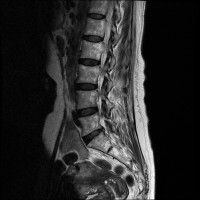

경추 요추 디스크 둘다 있는 상태고 경추몇번에서 몇번사이 요추몇번에서 몇번사이인지 알려주세요

허리

• 3번 째 사진